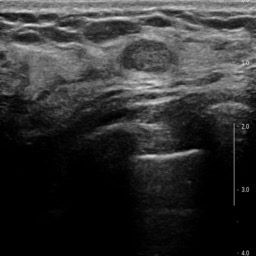

Ultrasonography is an important routine examination for breast cancer diagnosis, due to its non-invasive, radiation-free and low-cost properties. However, it is still not the first-line screening test for breast cancer due to its inherent limitations. It would be a tremendous success if we can precisely diagnose breast cancer by breast ultrasound images (BUS). Many learning-based computer-aided diagnostic methods have been proposed to achieve breast cancer diagnosis/lesion classification. However, most of them require a pre-define ROI and then classify the lesion inside the ROI. Conventional classification backbones, such as VGG16 and ResNet50, can achieve promising classification results with no ROI requirement. But these models lack interpretability, thus restricting their use in clinical practice. In this study, we propose a novel ROI-free model for breast cancer diagnosis in ultrasound images with interpretable feature representations. We leverage the anatomical prior knowledge that malignant and benign tumors have different spatial relationships between different tissue layers, and propose a HoVer-Transformer to formulate this prior knowledge. The proposed HoVer-Trans block extracts the inter- and intra-layer spatial information horizontally and vertically. We conduct and release an open dataset GDPH&GYFYY for breast cancer diagnosis in BUS. The proposed model is evaluated in three datasets by comparing with four CNN-based models and two vision transformer models via a five-fold cross validation. It achieves state-of-the-art classification performance with the best model interpretability.

翻译:超声波分析是乳腺癌诊断的一个重要常规检查,原因是其非侵入性、无辐射和低成本的特性。然而,由于其内在局限性,它仍不是乳腺癌的第一线筛选测试。如果我们能够精确地通过乳房超声图像诊断乳腺癌(BUS),它将是一个巨大的成功。我们提出了许多基于学习的计算机辅助诊断方法,以实现乳腺癌诊断/感官分类。然而,其中多数方法需要事先确定性能模型,然后对ROI内部的跨值进行分类。常规分类支柱,如VGG16和ResNet50等,可以在没有ROI要求的情况下实现有希望的分类结果。但是这些模型缺乏可解释性,从而限制了其在临床实践中的使用。在本研究中,我们提出了一个新的无乳腺癌诊断模型,在超声波图像中进行解释性特征描述。我们利用了先前的解剖学学学知识,即恶性肿瘤和良性肿瘤模型在不同组织层之间有着不同的空间关系,并提议采用状态解析法来编制这一先前的知识。拟议中的HOVer-Trans-Trading-Tradef-trainal Ex-deal-dealal-deal-deal-deal-degraphal-deal-deal-deal-deal-deal-deal disal disal-dal-dal-dal-dal-dal-deal-deal-dal-deal-deal-deal-dal-dal-dal-dal-dal-dal-dal-dal-dal-dal-dal-dal-dal-dal-I-dal-Iversal-dal-Ial-d-d-I-d-d-I-I-I-I-I-I-I-I-I-I-I-I-I-I-I-I-I-I-I-I-I-I-I-I-I-Ial-I-Ial-Ial-I-I-I-I-I-I-I-I-I-I-I-I-I-I-I-I-I-I-I-I-I-I-I-I-I-I-I-I-I-I-I-I-